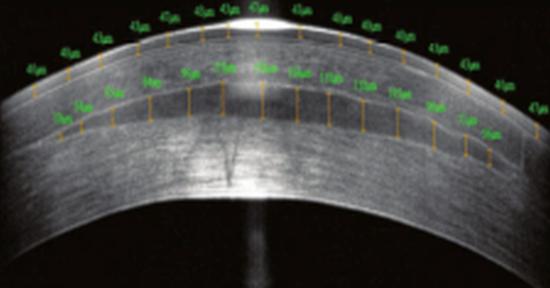

Biocompatible implants produced from donor human corneas can tackle prebyopia and other vision disorders, as an alternative to existing hydrogel implants. Credit: David Muller/Allotex.